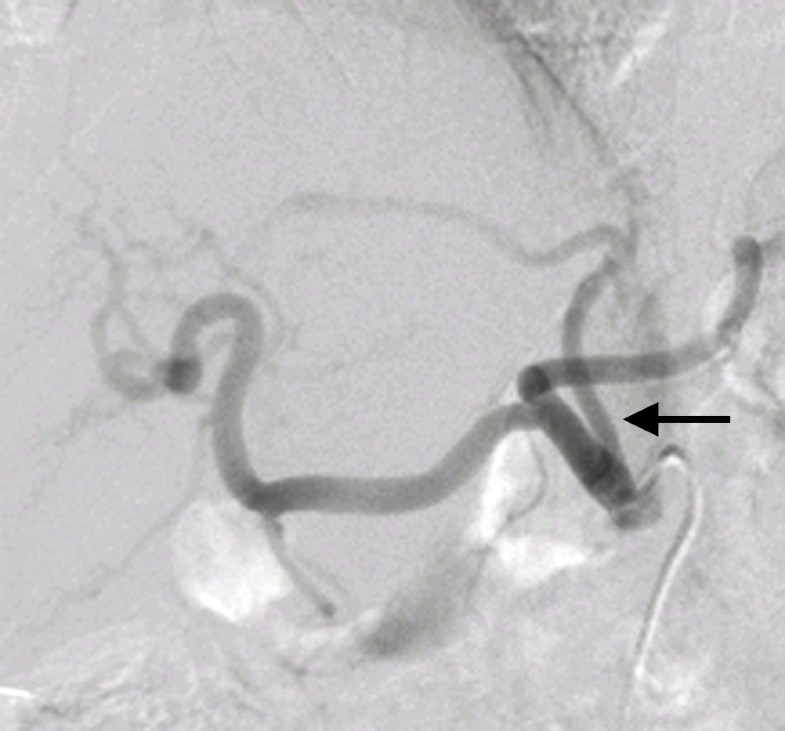

From www.researchgate.net

Figure4.The left gastric artery was treated using TAE with metallic Coil Embolization Of Gastric Artery Arteries primarily embolized were the gastroduodenal artery (n = 30), the left gastric artery (n = 18), the inferior pancreaticoduodenal. According to all available published evidence, empiric embolization assessed with endoscopic or preprocedural imaging findings (or both) appears to be as effective as targeted embolization in preventing rebleeding and mortality in patients with angiographically negative acute ugib. Eus enhances the. Coil Embolization Of Gastric Artery.